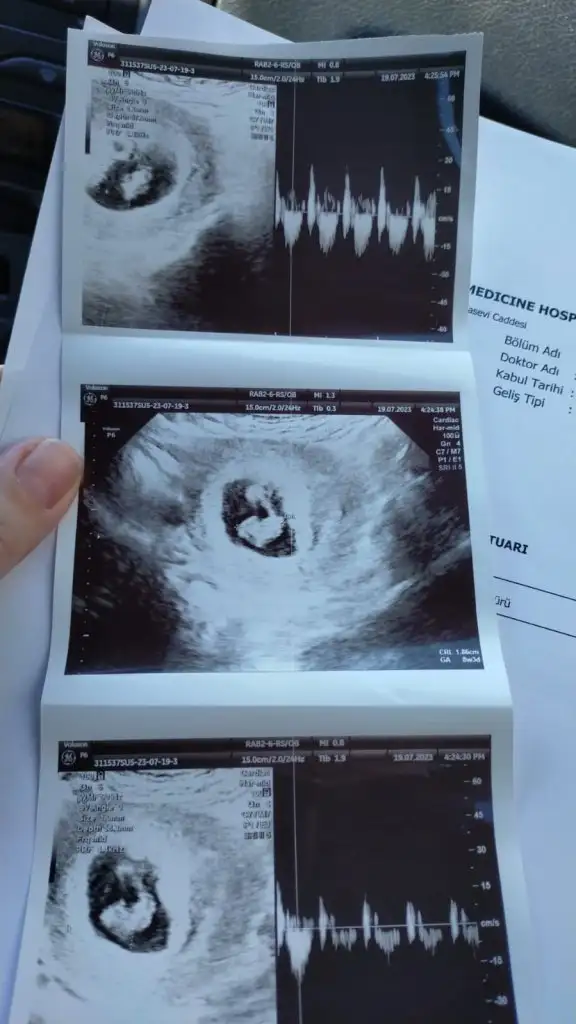

bana da yorum yapar mısınızErkek bebek büyük ihtimal saglıkla gelsin inşallah

Sanki orda pipi var gibi amabana da yorum yapar mısınız![]()

bu var bir deSanki orda pipi var gibi amatam bilemedim ilk hafta ultrason var mı canım

Erkek bebege benziyor kuzum saglıkla gelsin inşallahbu var bir de